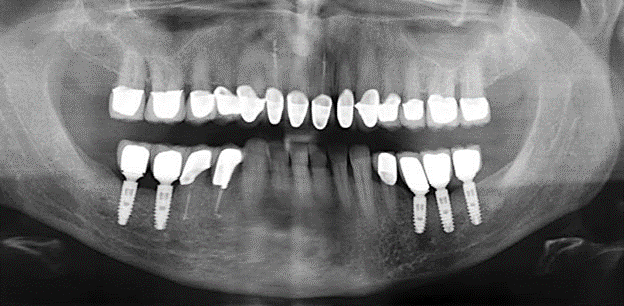

A 52-year-old patient presented in our clinic for the first time in 2004 following tooth loss in the third quadrant, expressing a desire for a new prosthetic restoration. Periodontal and radiological diagnostics revealed the need for extensive periodontological treatment. In addition, teeth 48, 28 and 27 were attributed a very poor prognosis and were subsequently extracted (Fig. 1). Following the successfully completed, systematic periodontological treatment, a fixed dental implant was inserted with the introduction of five implants in tooth regions 35, 36, 37, 46 and 47. Prosthetic treatment of the natural teeth was effected with veneered zirconium dioxide ceramic crowns; the implants were composed of two-piece, individual zirconium dioxide abutments and similarly veneered crowns made of a zirconium dioxide ceramic (Cercon base colored, Dentsply Sirona Lab). Definitive insertion of the prosthetic restoration occurred in 2005.

The ten-year check-up revealed no indications of advancing clinical attachment loss or peri-implant bone substance loss (Fig. 3).

Standardised and regular risk-adapted care in the scope of SPT is the key to treatment success for the clinical long-term success in periodontically compromised patients. This is particularly true for patients fitted with implants following successfully completed periodontal treatment (Fig. 11a and b).